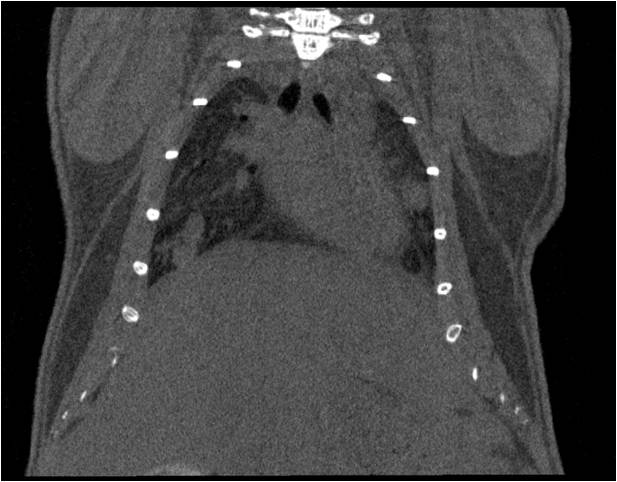

肺轉移

小鼠模式,22.5μm像素

正常

8天 14天

無造影劑注入 造影劑注入

心血管

胸部和心血管的層析成像 胸部和心血管的3D圖像